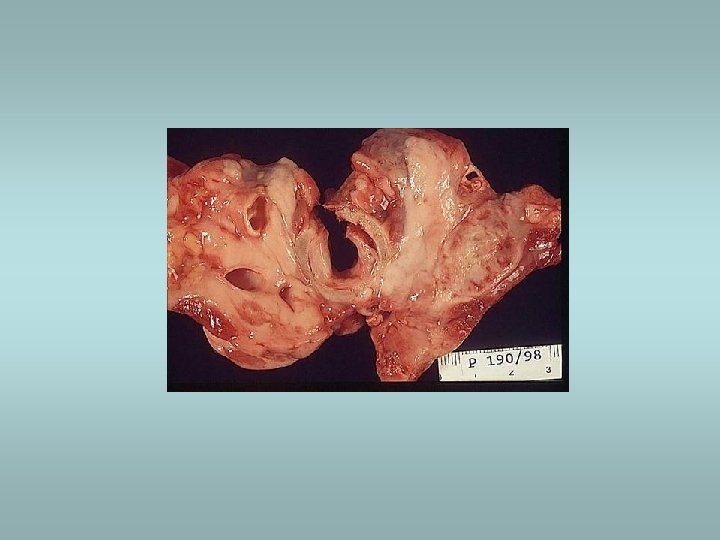

Parathyroid gland - tumors Adenoma ü Solitary, encapsulated – compression of adjacent gland ü No stromal fat ü Composed predominatly of chief cells ü Part of MEN I, MEN II Carcinoma ü Rare ü Invasion, metastases Hyperplasia ü All glands ü Fat cells interspersed

Parathyroid gland Primary hyperparathyroidism ü Hypersecretion of parathormone ü Caused by adenoma (80%), hyperplasia (15%), carcinoma (5%) ü Bone resorption, hypercalcemia – osteoporosis, muscle weaknes, nephrolithiasis, ulcers, pancreatitis, headache, depression Secondary hyperparathyroidism ü In patients with renal failure ü Compensatory hypersecretion of parathormone (reaction to phosphate retention and hypocalcemia)